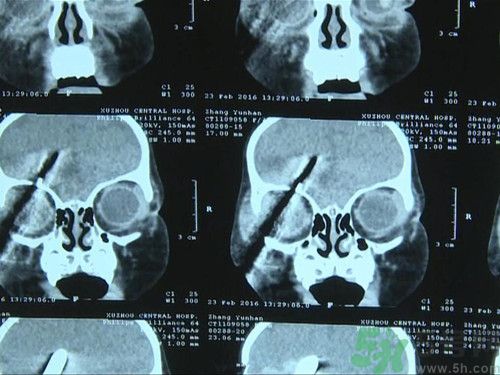

徐州女童名叫涵涵,今年只有1歲5個(gè)月。醫(yī)生發(fā)現(xiàn),螺絲刀已經(jīng)由面部斜插入涵涵的腦部,距離大血管僅有幾毫米。徐州市中心醫(yī)院腦外二科主任姜德華:“我看到這個(gè)小孩右側(cè)面部有一個(gè)螺絲刀從面部進(jìn)入插到頭部去了,從CT片子看,這個(gè)螺絲刀從眼眶部進(jìn)入到顱內(nèi),大概進(jìn)入頭面部有7厘米,其中進(jìn)入到顱內(nèi)有3厘米。小孩是昏迷的。”